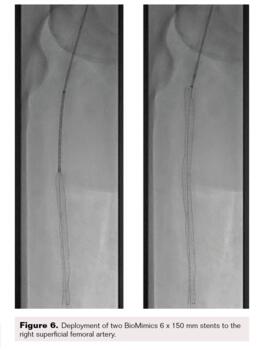

After the wire exchange, we attempted to aspirate, then flush, the 6F sheath with heparinized saline. After multiple failed attempts at sheath aspiration, we suspected a clotted arterial sheath and immediately proceeded to sheath exchange with a new 6F 45 cm sheath. Cautious to maintain wire position, the sheath was successfully exchanged. Saline flushing of the removed sheath resulted in expulsion of extensive clot burden (Figure 5). Repeat ACT confirmed therapeutic anticoagulation. The procedure concluded with percutaneous transluminal angioplasty followed by stenting of the SFA with BioMimics 6 x 150 mm stents (Figure 6). Final angiography demonstrated brisk flow through the SFA, popliteal, and anterior tibial arteries with no evidence of distal embolization (Figure 7 and Figure 8).